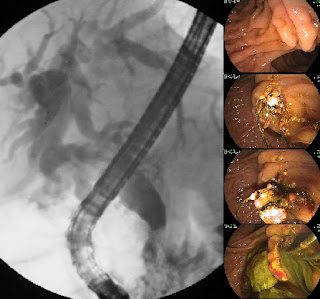

Colangitis en paciente diabética.

Mujer de 65 años, diabética, quien fue hospitalizada por cuadro de fiebre, escalofríos, no dolor abdominal. Durante su valoración se observó ictérica, bilirrubinas y fosfatasa que mostraban patrón obstructivo y ecografía con vía biliar dilatada y colelitiasis.

Se realiza CPRE y se encuentra papila muy abombada con expulsión espontánea de pus. Se contrastó vía biliar de 14 mm con defectos de llenado en su interior. La vesícula se contrastó con defectos de llenado. Se realizó papilotomía y se extrajo varios cálculos secundarios, pus densa. Se observó aerobilia.